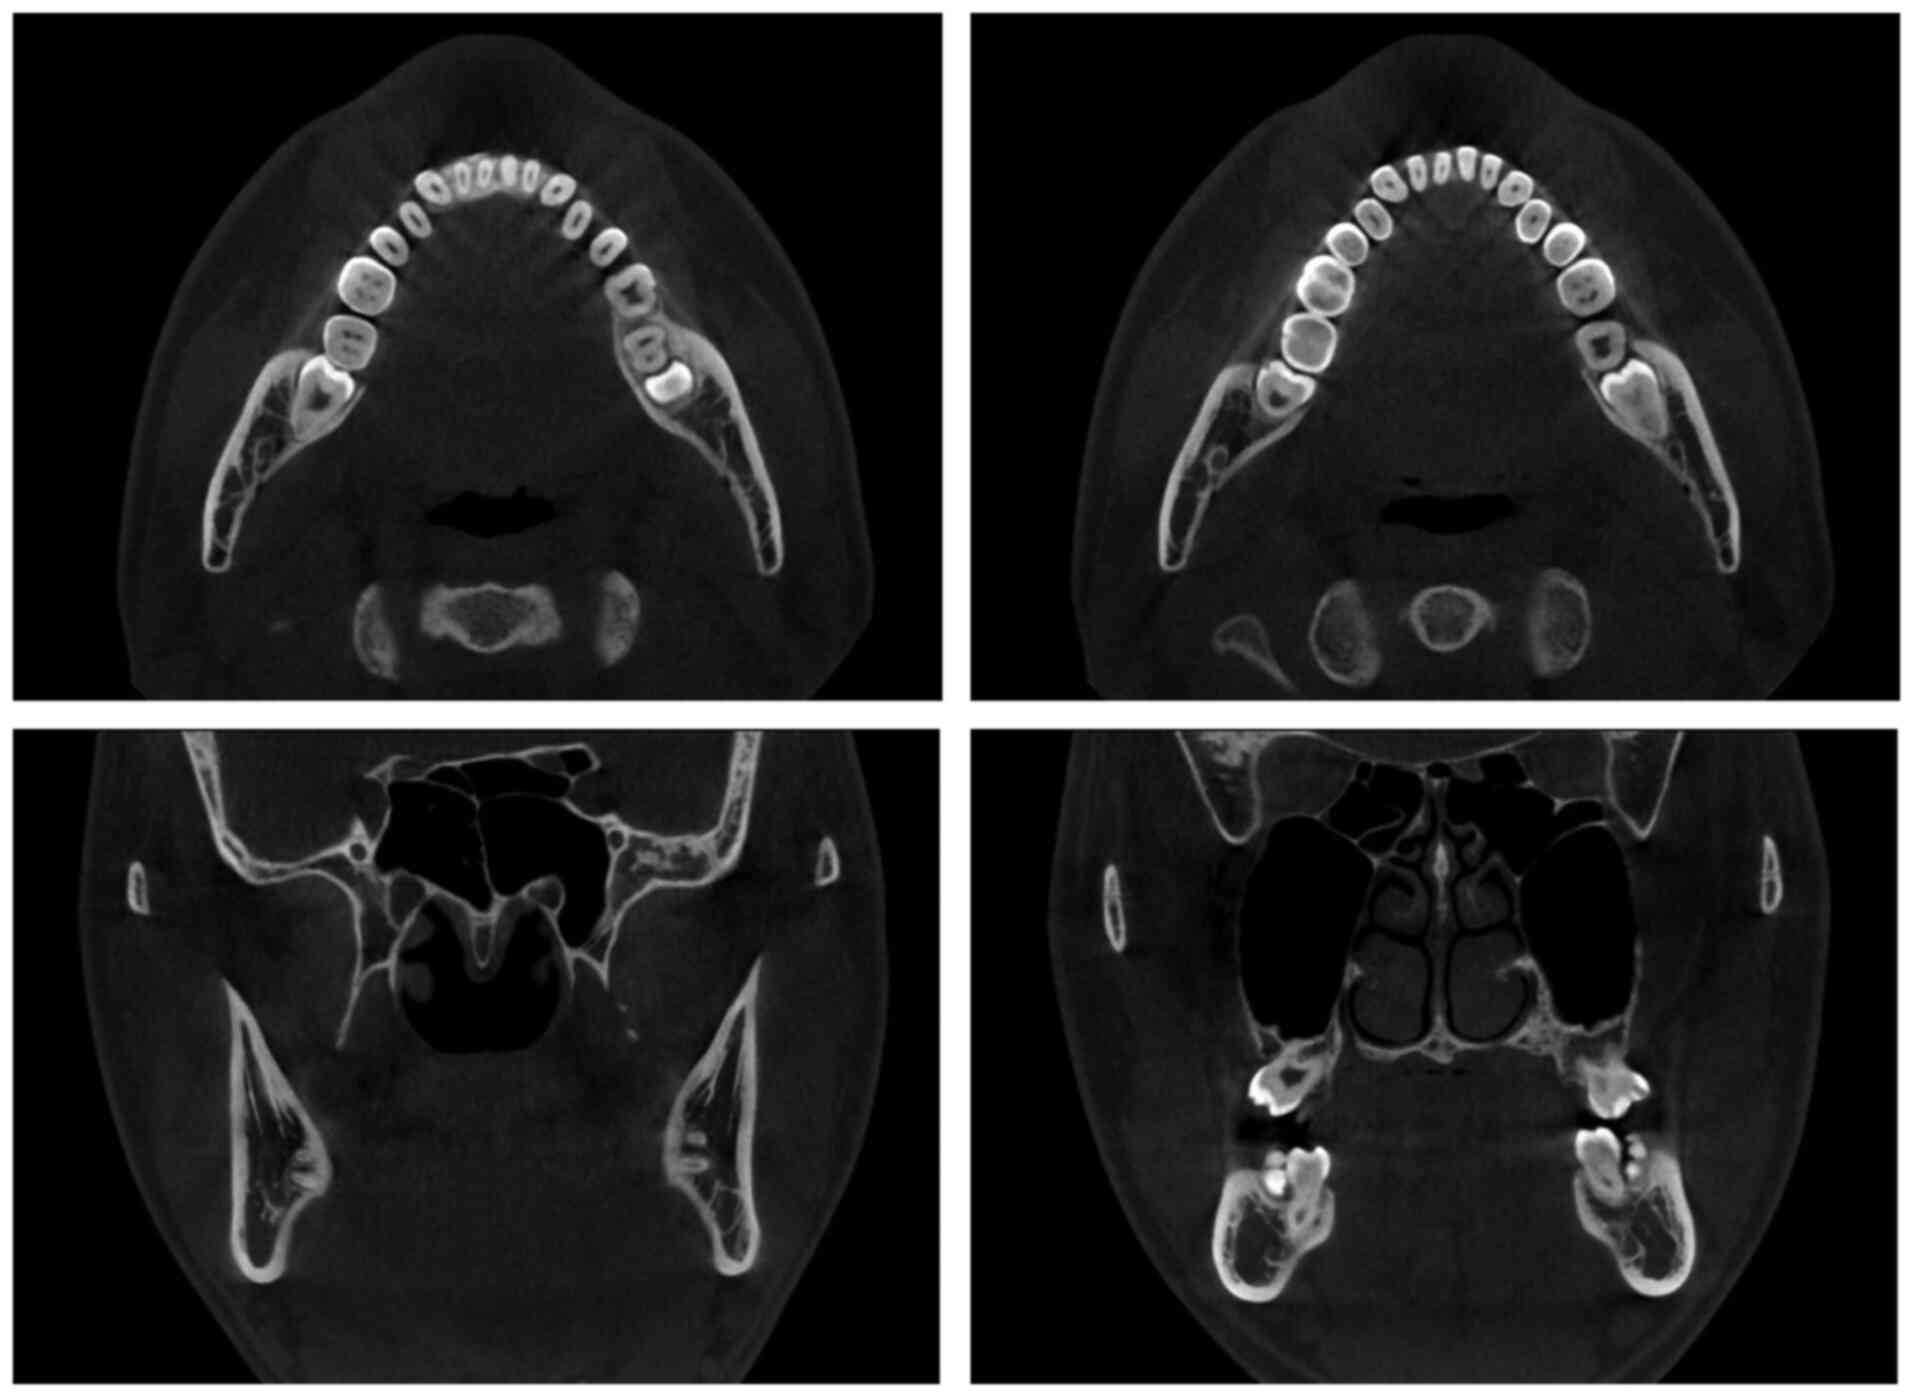

Oral/dental surgical care in patients with chronic medical comorbidities, such as isovaleric acidemia (IVA), can be challenging. In addition to technical complications, different comorbidities also present a complex range of concerning factors/challenges, which can increase the incidence of morbidity and mortality associated with surgery. IVA, a congenital error of metabolism, is a rare organic acidemia with a predisposition towards acute acidosis and life‑threatening metabolic decompensation during stressful conditions, such as prolonged fasting and surgery. In addition, schizophrenia, a major neurological disorder, can result in manifestation of severe dental or periodontal conditions, including pericoronitis. The condition is associated with significant risk factors of postoperative complications, such as dangerous behaviors and adverse interactions between antipsychotic drugs and anesthetic agents. A case of comorbid dental disease with two coexisting chronic and life‑threatening medical conditions, one of which is rare, is an unusual encounter in oral/dental surgery that is seldomly published. Moreover, implementing a safe and effective surgical intervention in such patients requires several informed considerations. However, only a few reported experiences or guidelines exist, reporting appropriate perioperative management strategies to minimize risks. Hence, in this case report, our experience of managing one of these rare encounters of a 20‑year‑old man who suffered from bilaterally partially erupted third molars, associated with chronic pericoronitis and dental caries of both the maxilla wisdom teeth with coexisting IVA and schizophrenia comorbidities is described. Additionally, the presentation and anticipated complications of the comorbid disorders of the patient are briefly reviewed. In this case, the pericoronitis and dental caries were treated by surgically removing the impacted third molars and the antagonist maxilla wisdom teeth under regional anesthesia and application of antibiotics for 3 days. The patient recovered without any postoperative complications after 1 year of follow‑up.

Figure 1

Figure 2

Figure 3

Figure 4